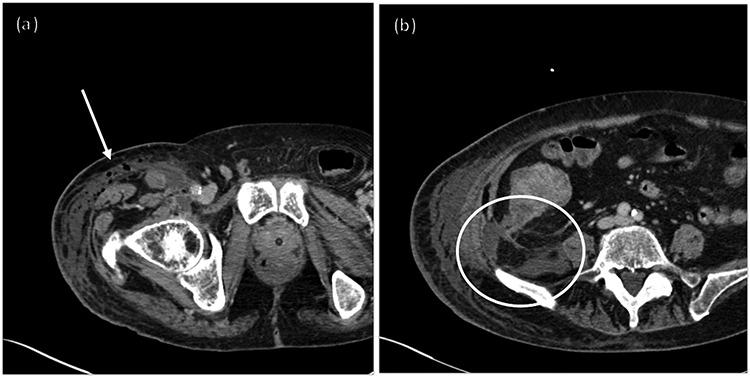

一例继发于盲肠癌穿孔的坏死性筋膜炎非典型病例。

An atypical case of necrotizing fasciitis secondary to perforated cecal cancer.

Necrotizing fasciitis is an aggressive, life threatening soft tissue infection that requires high index of suspicion for diagnosis. Diagnosis is clinical with management including broad spectrum antibiotics and emergent operative debridement. The majority of cases are secondary to underlying medical processes, local tissue damage, abscess, or inciting procedure, with a paucity of data correlating causation with colon cancer. We describe the case of an 84-year-old man presenting with sepsis of unknown origin who was diagnosed with an atypical presentation of necrotizing fasciitis secondary to a perforated cecal malignancy. His case is unique in that a less virulent polymicrobial infection was likely involved as he initially improved with conservative management alone. He ultimately declined and expired secondary to overwhelming sepsis from his infection. This case highlights the importance of maintaining a high index of suspicion for necrotizing infection and considerations for alternative etiologies of infection including perforated malignancies.

摘要

坏死性筋膜炎是一种侵袭性、危及生命的软组织感染,诊断时需要高度怀疑。诊断依靠临床判断,治疗包括使用广谱抗生素和紧急手术清创。大多数病例继发于潜在的医疗过程、局部组织损伤、脓肿或诱发手术,与结肠癌相关的病因数据较少。我们描述了一名84岁男性患者的病例,该患者出现不明原因的败血症,被诊断为盲肠恶性肿瘤穿孔继发的坏死性筋膜炎非典型表现。他的病例独特之处在于,可能涉及毒性较低的混合微生物感染,因为他最初仅通过保守治疗就有所好转。他最终病情恶化,因感染导致的严重败血症而死亡。该病例强调了对坏死性感染保持高度怀疑的重要性,以及对包括恶性肿瘤穿孔在内的感染替代病因的考虑。